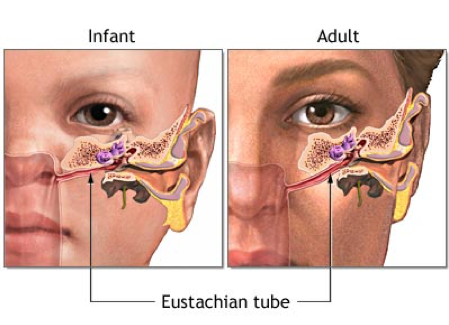

Why are infants more prone to ear infections than adults?

As they have a smaller and more horizontal Eustachian tube –> more direct route for infections to access the tube and therefore the middle ear

As we grow, how does our Eustachian tube change shape?

Becomes more vertical with age